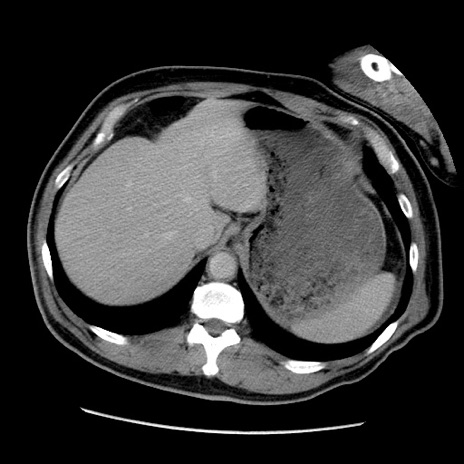

症例

冠状断像